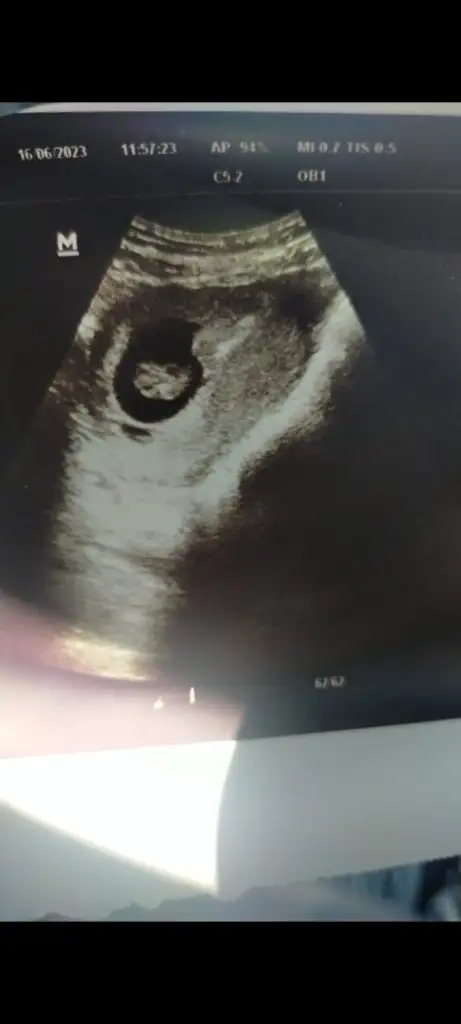

7+5 haftalık ultrason olması lazım şuan 12+2deyiz ama en eski bu olduğu için bunu attım cinsiyet tahmini yapabilen var mı? 😊

Eklentiler

• Screenshot_2023-07-10-17-33-05-17_6012fa4d4ddec268fc5c7112cbb265e7.webp

Screenshot_2023-07-10-17-33-05-17_6012fa4d4ddec268fc5c7112cbb265e7.webp

10,2 KB · Görüntüleme: 44